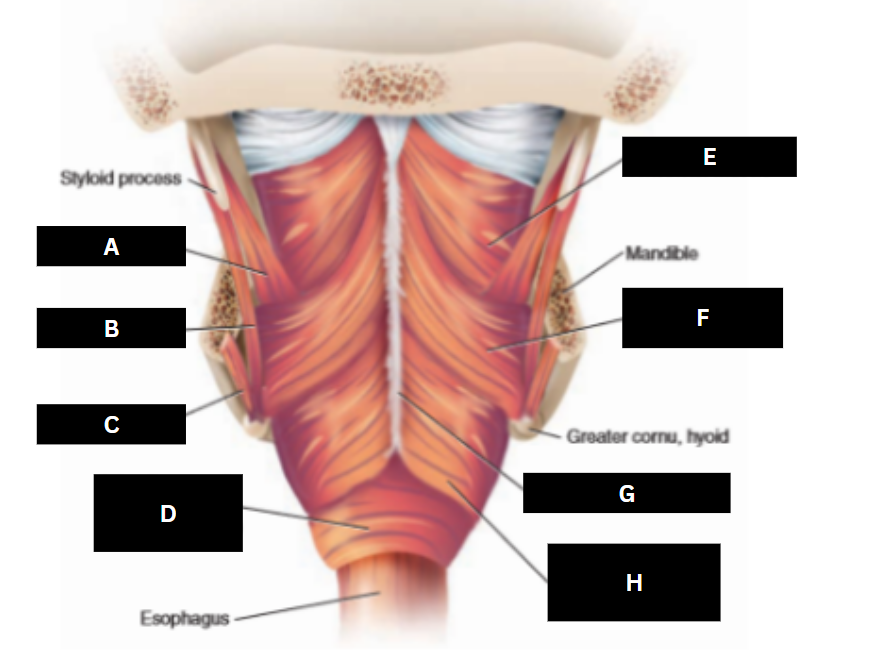

Stylopharyngeus

A

Styloglossus

B

Stylohyoid

C

Cricopharyngeus

D

Superior pharyngeal constrictor

E

Middle pharyngeal constrictor

F

Pharyngeal raphe

G

Inferior pharyngeal constrictor

H